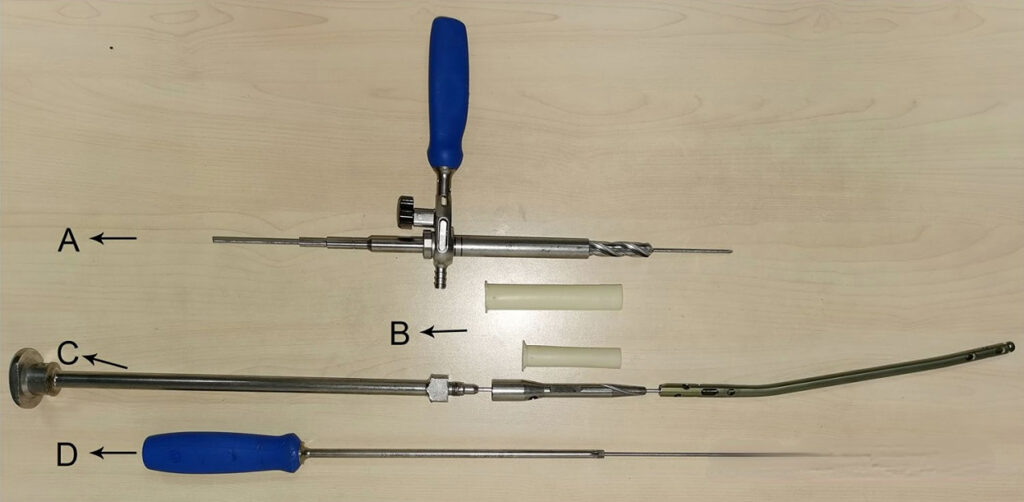

First, find the needle insertion point of the tibial intramedullary nail and locate the tail cap. The author uses a 3.2mm guide needle and confirms it through intraoperative fluoroscopy (under the current circumstances, is it a bit of a luxury to remove the nail with a guide needle?):

The patellofemoral joint usually becomes scarred due to the original surgical trauma, resulting in a tight patellofemoral joint. It may be difficult to directly insert the protective sleeve, or it may be difficult to move after insertion (stuck in the intercondylar notch of the femur). However, it is relatively simple to insert the protective sleeve through a guide needle. After inserting the sleeve, use a drill bit to remove the callus and soft tissue around the tail cap, and use a hollow screwdriver to remove the tail cap.

After the tail cap is removed, the guide pin is inserted. After the nail removal tool is screwed into the tail of the intramedullary nail and firmly fixed, the distal locking screw is removed and the main nail of the intramedullary nail is removed by hammering. Note that the locking screw at the proximal end of the intramedullary nail can be removed first in the first step, but the distal locking screw must be removed after the tail cap is removed and the nail removal tool is fixed to the tail of the intramedullary nail to avoid axial movement or rotation of the intramedullary nail during the operation.